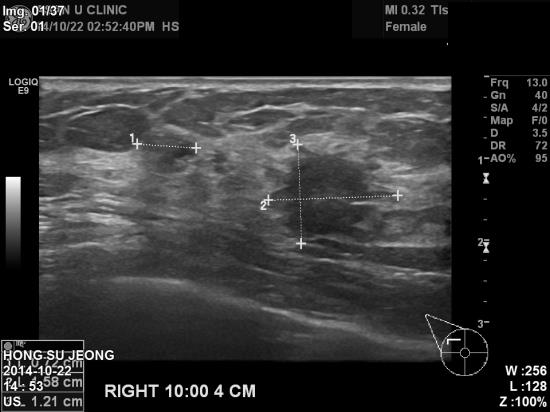

타병원에서 유방초음파 시행 후 우측 1cm 혹 소견보여

본원에 내원하신 48세 여성분이십니다

본원 초음파상 우측 10시 방향에 1.58cm혹 발견되어

조직검사 시행 후 침윤성유관암으로 진단되었습니다